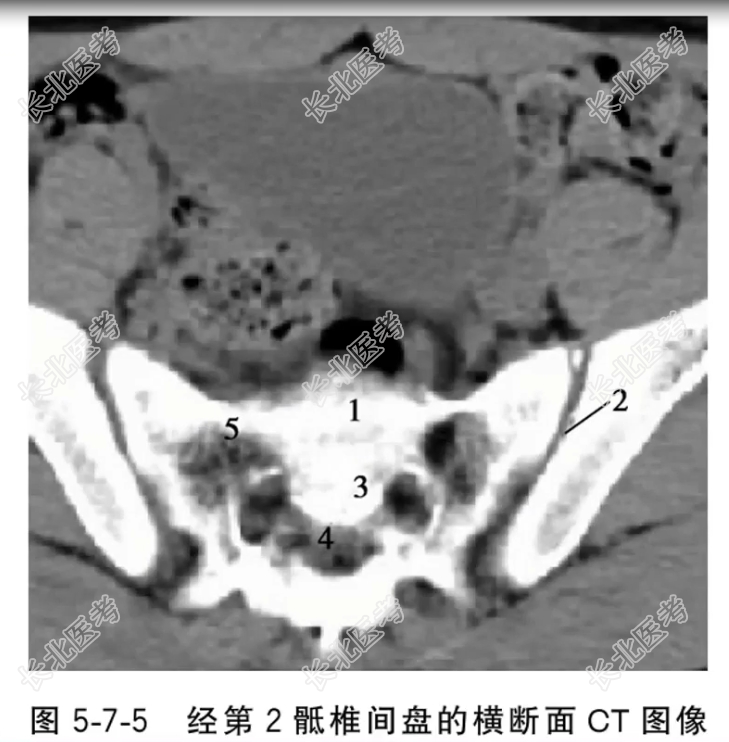

- 单项选择题经第2骶椎间盘的横断面CT图像中,标记为2、4的结构分别是

A、骶髂关节、骶管

B、骶管、骶髂关节

C、第2骶椎、骶前孔

D、骶前孔、第2骶椎

E、第2骶椎间盘、骶髂关节